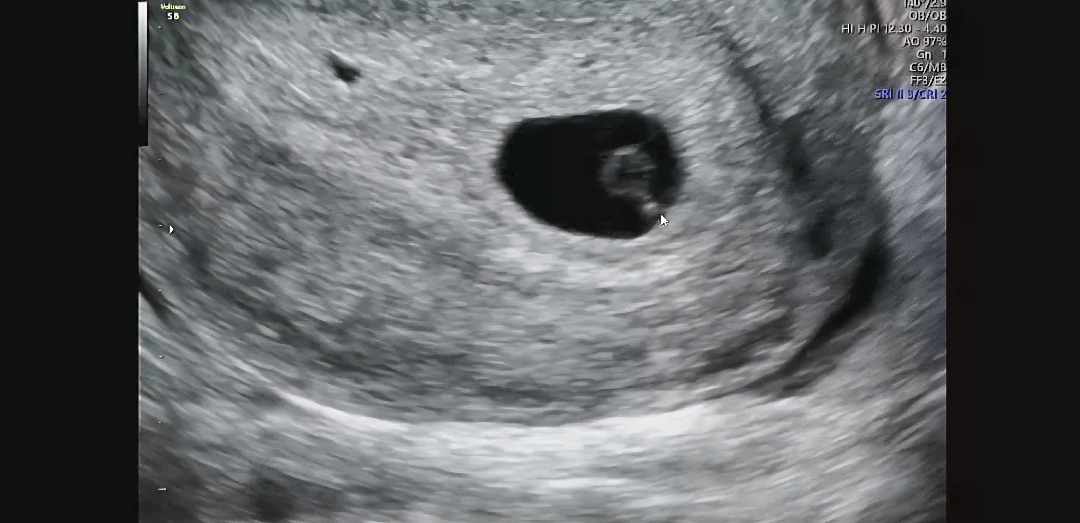

아기집 옆에 피고임인가요?

오늘 초음파를 보고 왔는데 5주 5일이라고 하네요. 근데 아기집 왼쪽에 보이는건 피고임일까요? 집에와서 보니 저거 뭔가 싶어서요 선생님은 피고임은 없다고 하셨었어요

피고임 아니구 그냥 복강인것같아요!!